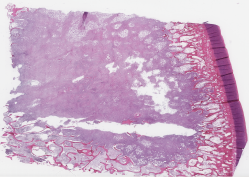

Category Train Validation Image Example

(No-Count) Lipomas 703 176 [Uncaptioned image]

(No-Count) Non-neoplastic lesions 400 100 [Uncaptioned image]

(No-Count) Skin punch biopsies 180 45 [Uncaptioned image]

(No-Count) Skin&subcutaneous tissues 522 131 [Uncaptioned image]

Table 1: Biopsy slide classification data